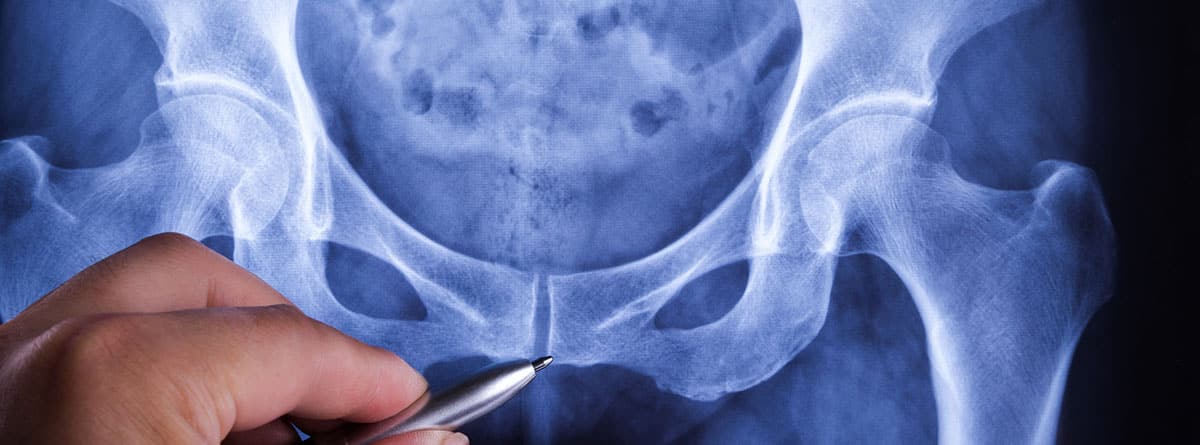

¿Qué es el suelo pélvico?

El suelo pélvico es un grupo de músculos que forma la base de la pelvis y que va desde el cóccix por detrás hasta el hueso púbico por delante.

La musculatura del suelo pélvico aguanta y actúa como soporte de los órganos pélvicos (vejiga urinaria, próstata en hombres, recto, vagina y útero en mujeres).